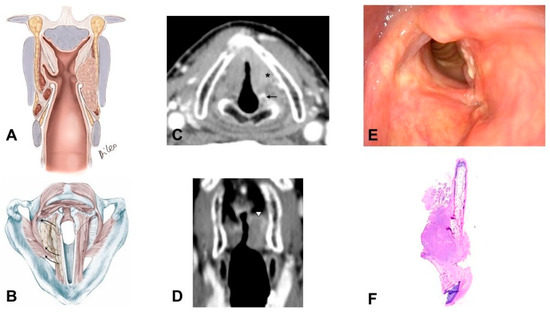

- Supraglottic carcinoma encasing the arytenoid from above with its fixation due to weight effect, without direct involvement of the CAU (Figure 2):

- The tumor infiltrates the superior paraglottic space (SPGS) and the thyro-arytenoid muscle (TAM) without direct involvement of the crico-arytenoid unit (CAU), with evaluation of the following radiological parameters: superior paraglottic space (SPGS), TAM, inferior paraglottic space (IPGS), crico-arytenoid joint (CAJ) and cricoid plate.